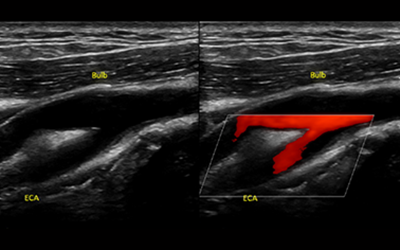

경동맥 초음파 검사는 목 부위에 위치한 경동맥의 상태를 실시간으로 확인할 수 있는 비침습적인 검사 방법입니다. 초음파를 이용하여 혈관 벽의 두께, 혈액의 흐름, 혈관 내 플라크(혈전)의 존재 여부 등을 파악할 수 있습니다. 마치 도로 위에 설치된 CCTV처럼, 혈관 속 상황을 안전하게 들여다보는 것이죠. 검사 과정은 간단하며, 통증이나 불편함이 거의 없어 누구나 부담 없이 받을 수 있습니다.

경동맥 초음파 검사는 다양한 경동맥 질환을 진단하는 데 유용한 도구입니다. 다음은 경동맥 초음파 검사를 통해 확인할 수 있는 주요 질환들입니다.